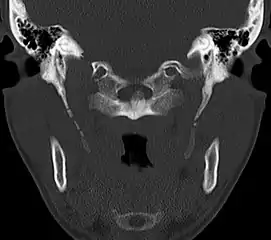

CT scan, coronal section showing bilateral extended styloid process and stylohyoid ligament ossification (incidental finding)

Diagnosis is suspected when a patient presents with the symptoms of the classic form of "Eagle syndrome" e.g. unilateral neck pain, sore throat or tinnitus. Sometimes the tip of the styloid process is palpable in the back of the throat. The diagnosis of the vascular type is more difficult and requires an expert opinion. One should have a high level of suspicion when neurological symptoms occur upon head rotation. Symptoms tend to be worsened on bimanual palpation of the styloid through the tonsillar bed. They may be relieved by infiltration of lidocaine into the tonsillar bed. Because of the proximity of several large vascular structures in this area this procedure should not be considered to be risk free.

Imaging is important and is diagnostic. Visualizing the styloid process on a CT scan with 3D reconstruction is the suggested imaging technique.[12] The enlarged styloid may be visible on an orthopantogram or a lateral soft tissue X ray of the neck.